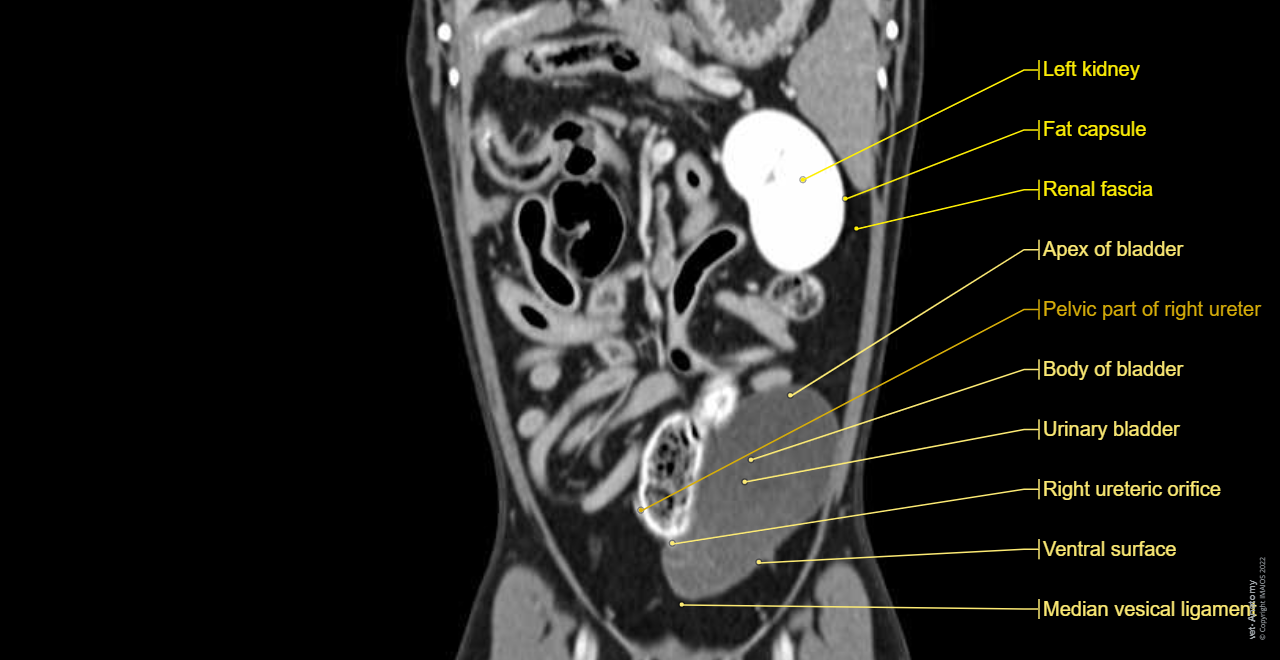

Dog - Urinary organs: Kidney, Ureter, Urinary bladder, Male urethra

Dog